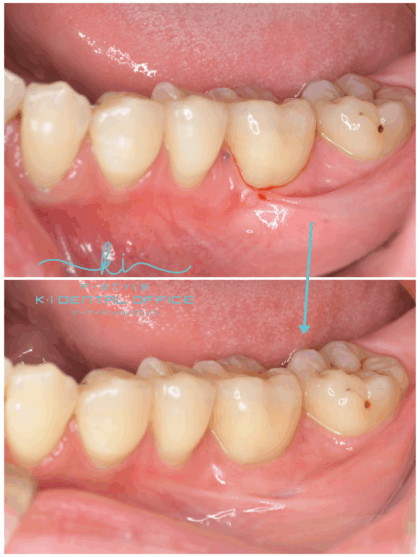

根面被覆術

歯ぐきが下がり見た目が悪くなったり、知覚過敏があったりした場合に、歯ぐきを移植して下がった歯ぐきを修復する治療法です。